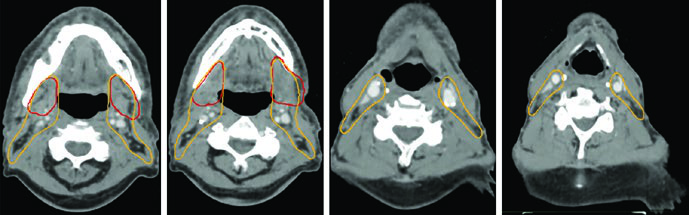

Além da endoscopia com fibra óptica, imagens diagnósticas de alta qualidade são críticas para a localização tumoral. Cada modalidade de imagem tem seu papel específico:

A TC de alta resolução dos seios paranasais com contraste IV e cortes finos de 1–2 mm é ideal para visualizar erosão cortical óssea precoce. A RM com contraste IV e sequências com supressão de gordura, em cortes finos, é superior para avaliar extensão em partes moles, extensão intracraniana, invasão perineural e envolvimento dos forames e canais dos nervos cranianos. O PET/CT complementa o estadiamento ao identificar linfonodos suspeitos e doença metastática.

O GTV deve ser delineado usando todas as informações clínicas relevantes de endoscopia, TC, RM e PET. O CTV de alto risco deve cobrir todos os sítios iniciais de doença e regiões potenciais de disseminação subclínica. Todas as imagens pré-operatórias devem ser avaliadas para garantir que o volume tumoral inicial esteja coberto.

A RM deve ser usada em todos os casos para auxiliar o delineamento, exceto quando contraindicada. Carcinomas adenoides císticos são altamente neurotrópicos, portanto os volumes devem cobrir nervos aferentes e eferentes locais até a base do crânio. ENB surge na cavidade nasal superior e tende a invadir a lâmina cribriforme e fossa craniana anterior precocemente.